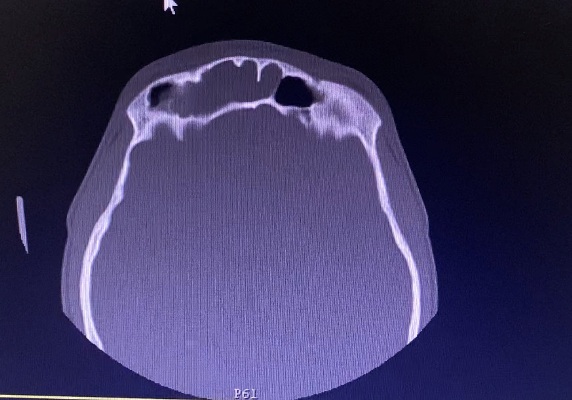

Пациенту, с согласия мамы, было произведено КТ ППН, по результатам которого был поставлен диагноз: «Острый полисинусит. Искривление перегородки носа. Вазомоторный ринит».

Снимки до начала лечения